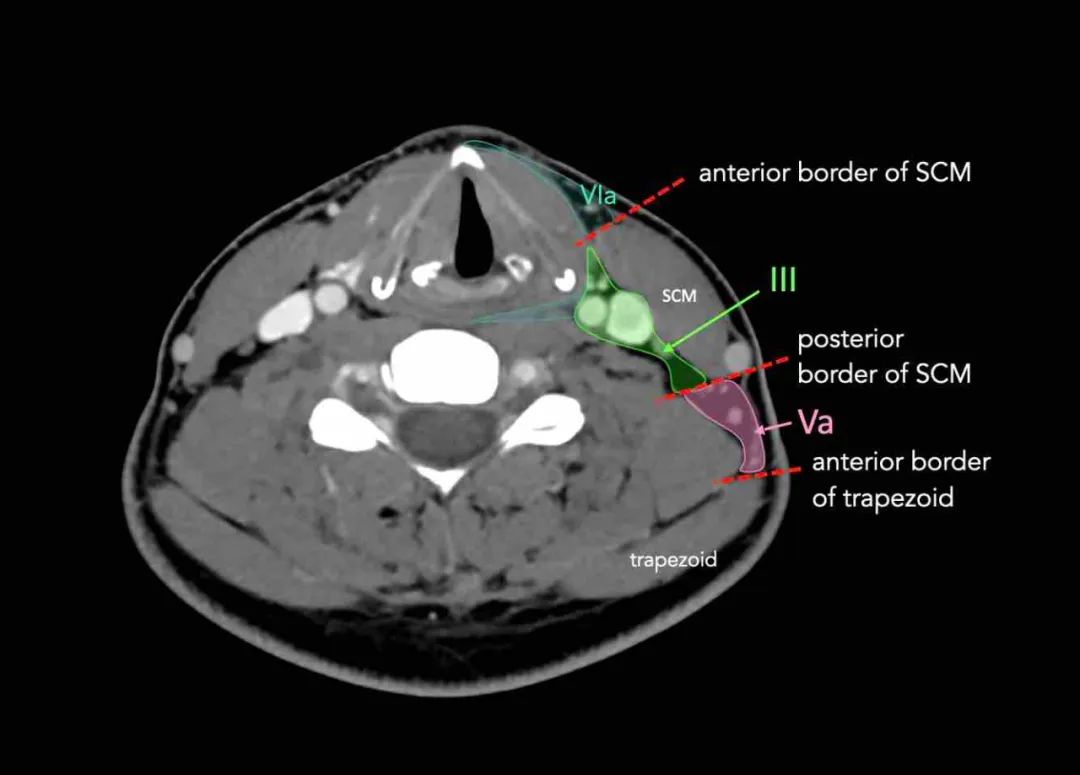

III -中颈静脉III级接受来自II级和V级的传出淋巴管,以及来自咽后、气管前和喉返淋巴结的一些传出淋巴管。

它从舌根、扁桃体、喉、下咽部和甲状腺收集淋巴管。

环状软骨的下缘是III和IVA之间的边界。III级淋巴结有来自口腔、鼻咽、口咽、下咽和喉的癌症转移的风险。